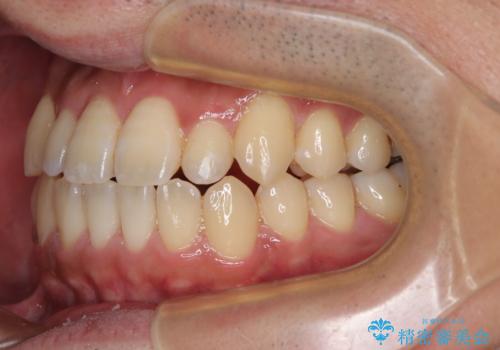

内側に引っ込んだ歯を治したい インビザラインの矯正治療

- 前歯のデコボコとクロスバイトを治したいとのことで来院された患者様です。

上下顎ともに歯列全体の側方拡大とIPR(歯と歯の間を削る)によってデコボコとクロスバイトが解消するように設計し、インビザラインにより治療を行うこととしました。

反対咬合特有の治療途中の前歯の干渉が長く続き、治療中に食事をとりにくく、ご迷惑をおかけしました。

前歯の咬み合わせの調整などを行い、安定した咬み合わせに仕上げることができました。